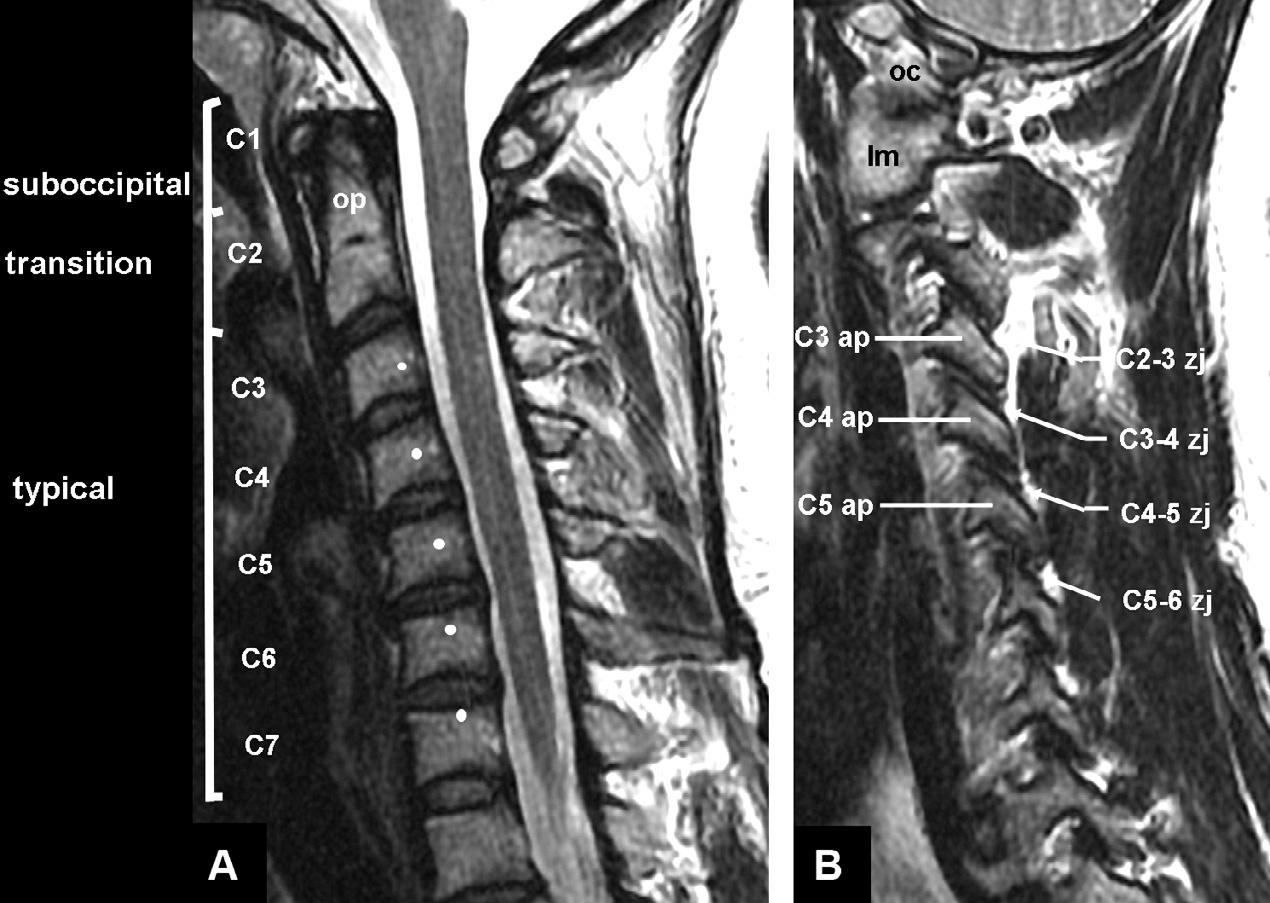

Bothfordescriptivepurposesandfunctionally,the cervicalspinecanbedividedintothreezones:thesuboccipitalzone,centeredontheC1vertebra;atransitional zoneformedbytheC2vertebra;andthetypicalzone, encompassingtheC–7vertebrae(BogdukandMercer, 2000)(Fig.32.1).Thesezonesdifferbothinstructure andinfunction.

Fig.32.1. Sagittalmagneticresonanceimagesofthecervicalspine,showingitsstructureandzones.(A)Medianscan,showing thevertebralbodiesandinterverterbraldiscs.Thewhitedotsmarkthemeanlocationoftheaxesofrotationforflexion-extensionof thevertebraabove.Theodontoidprocess(op)projectsrostrallyfromthebodyofC2,toliebehindtheanteriorarchoftheatlas(C1). (B)Lateralscan,showingtheoccipitalcondyle(oc),thelateralmass(lm)oftheatlas(C1),thearticularpillars(ap),andthezygapophysialjoints(zj)thattheyform,atthesegmentslabeled.(CourtesyofDr.TimMaus,MayoClinic,Rochester,MN.)